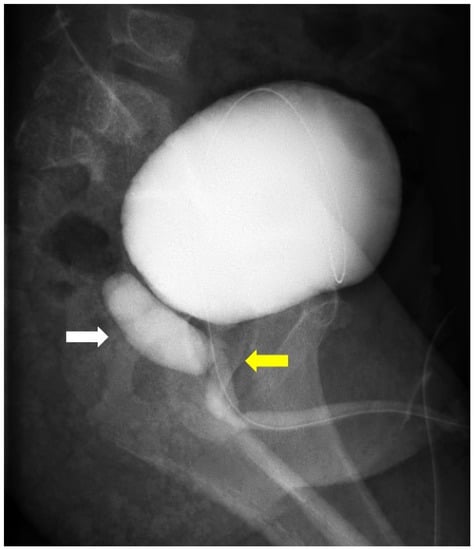

2. Case Presentation